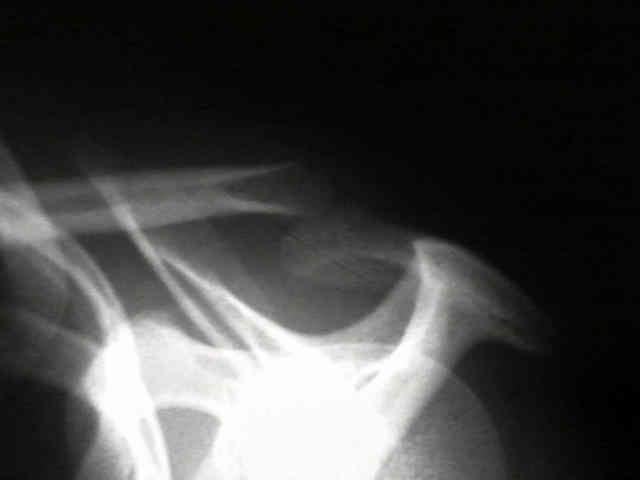

AC Joint 1 AC Joint 2 AC Joint 3 AC Joint 4

• 20-year-old who fell on tip of right shoulder, but did not show radiographic signs of AC joint injury in the ER;

• one month later the patient continued to have pain, and radiographs demonstrated greater than 100 percent displacement of AC joint on both AP and Cross Body AP (Cross Adduction View);